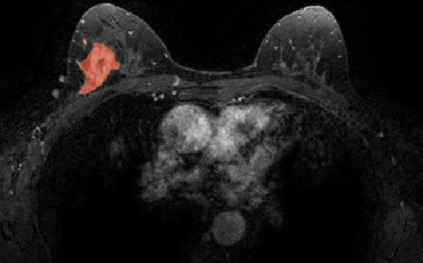

Most papers caution against using predictive models for disease stratification based on unselected radiomic features, as these features are affected by contouring variability. Instead, they advocate for the use of the Intraclass Correlation Coefficient (ICC) as a measure of stability for feature selection. However, the direct effect of segmentation variability on the predictive models is rarely studied. This study investigates the impact of segmentation variability on feature stability and predictive performance in radiomics-based prediction of Triple-Negative Breast Cancer (TNBC) subtype using Magnetic Resonance Imaging. A total of 244 images from the Duke dataset were used, with segmentation variability introduced through modifications of manual segmentations. For each mask, explainable radiomic features were selected using the Shapley Additive exPlanations method and used to train logistic regression models. Feature stability across segmentations was assessed via ICC, Pearson's correlation, and reliability scores quantifying the relationship between feature stability and segmentation variability. Results indicate that segmentation accuracy does not significantly impact predictive performance. While incorporating peritumoral information may reduce feature reproducibility, it does not diminish feature predictive capability. Moreover, feature selection in predictive models is not inherently tied to feature stability with respect to segmentation, suggesting that an overreliance on ICC or reliability scores for feature selection might exclude valuable predictive features.